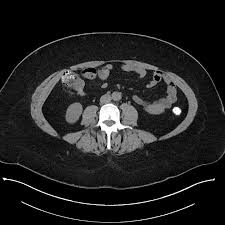

A Pedunculated Adenoma In The Terminal Ileum Springerlink

A Pedunculated Adenoma In The Terminal Ileum Springerlink from media.springernature.com